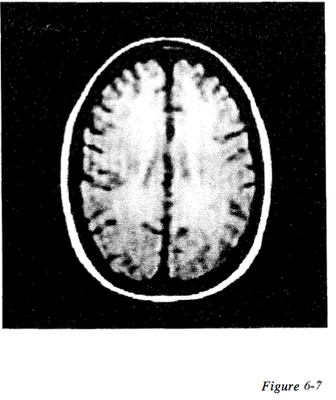

Question 60

Question

Figure 6-5 displays an example of what type of artifact

Answer

• Truncation

• Aliasing

• Cross excitation

• Chemical shift

Question 61

Figure 6-6 displays an example of what type of artifact

• Phase mismapping

Question 62

Figure 6-7 displays an example of what type of artifact